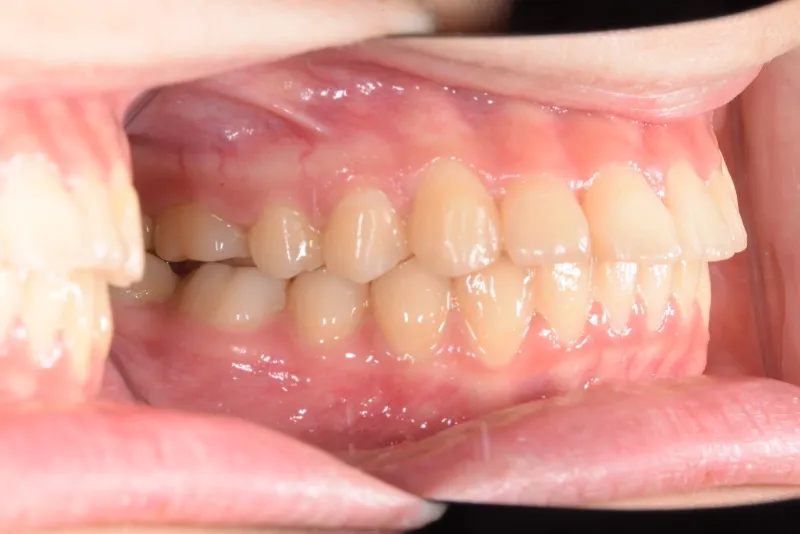

• 治療終了後

治療終了後

乳歯があるうちは上下オリジナル固定装置を利用し、永久歯が生えそろったらマルチブラケット装置を利用して治療しました。

治療回数35回、5年9ヶ月の治療期間で矯正治療を終了しました。